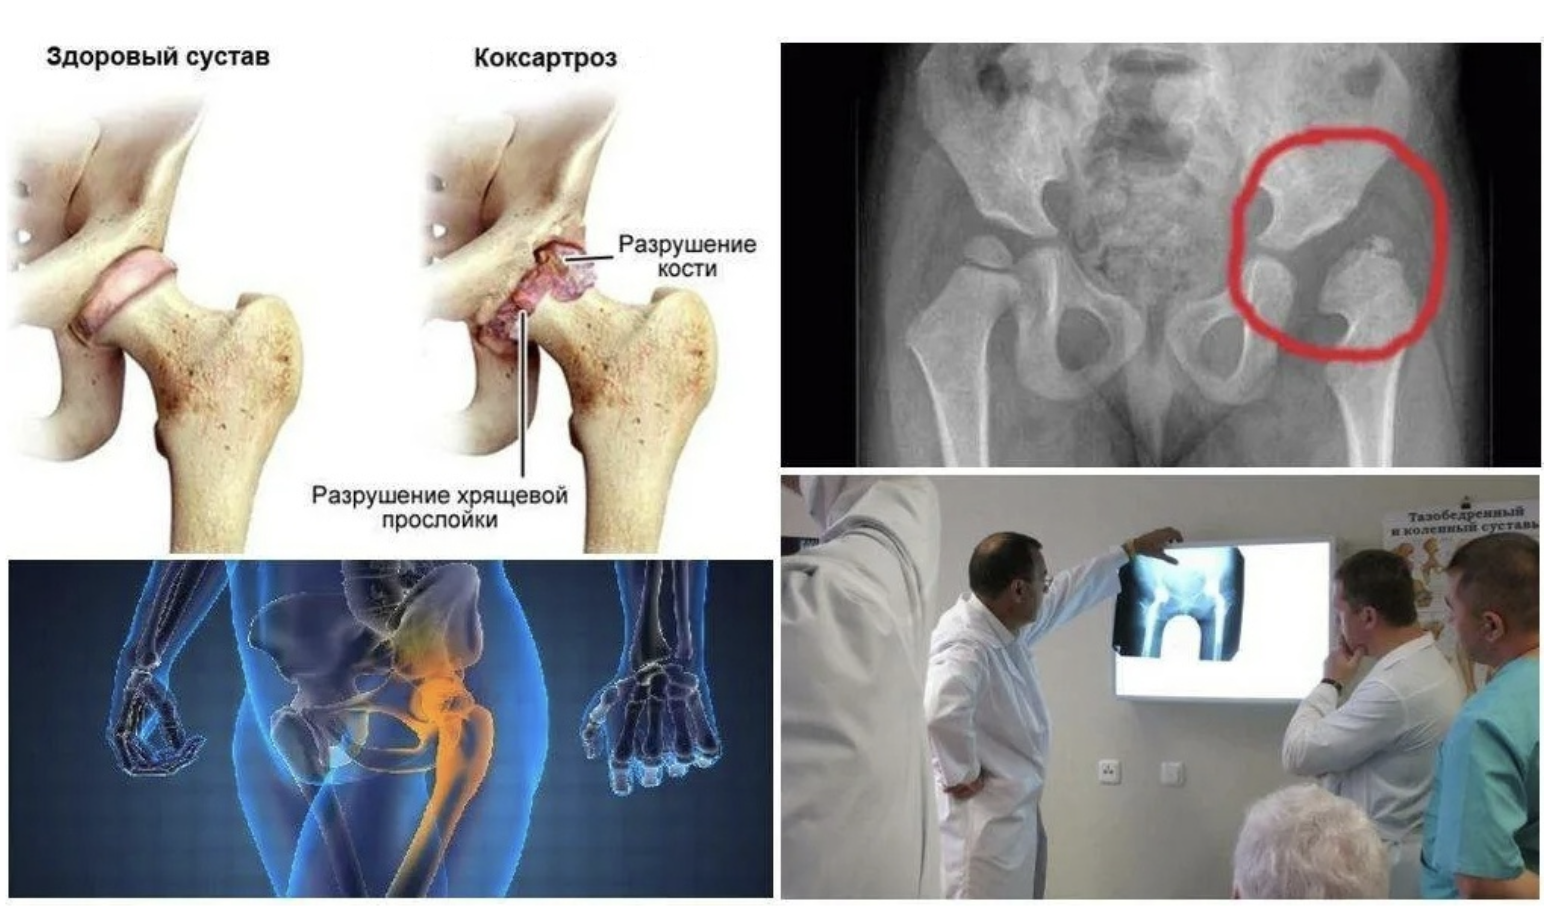

Синовит тазобедренного сустава – это воспаление синовиальной оболочки, которое может привести к болям и ограничению подвижности. Важно своевременно обращаться к специалисту и соблюдать комплексное лечение, включающее как медикаментозную терапию, так и рекомендации по физиотерапии и образу жизни. В этой статье вы найдете полезные советы по облегчению симптомов и ускорению выздоровления.

💊 Какие препараты необходимо принимать при диагнозе «коксартроз»? Препараты при коксартрозе. 18+

Операция тазобедренного сустава: делать или нет. Эндопротезирование.